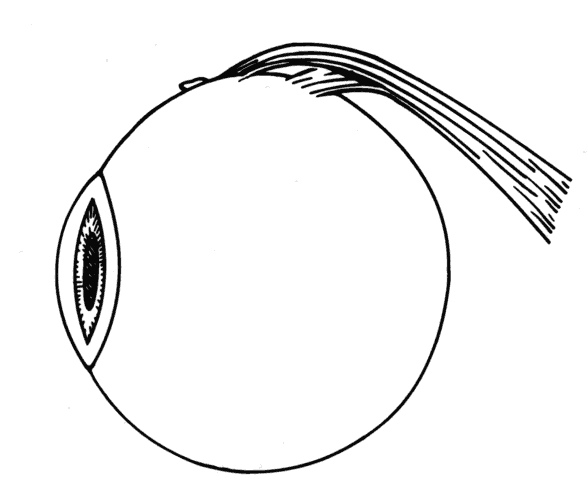

After the incision has been made and the dissection through Tenon's capsule has been completed to the surface of the sclera, muscle hooks are passed behind the rectus muscle to identify the insertion of the muscle. Once the muscle has been “hooked,” there is improved control of the globe. This will facilitate the blunt and sharp dissection that will be needed to reflect the conjunctiva over the tendon of the muscle (Fig. 15). Sharp dissection beneath the conjunctiva is used to separate fibrous tissue and restrictive bands from the surface of the muscle capsule and the sclera (Figs. 16 and 17). Frequently it will be necessary to remove small amounts of tissue to visualize the area of contact of the muscle insertion (Fig. 18).

Fig. 15. A Jameson muscle hook is under the insertion of a previously recessed horizontal rectus muscle. The insertion is cleared of any residual adhesive bands and scar tissue.